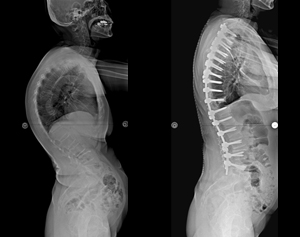

病例一 |

| 術前 |

術後 |

| 側向X光片 |